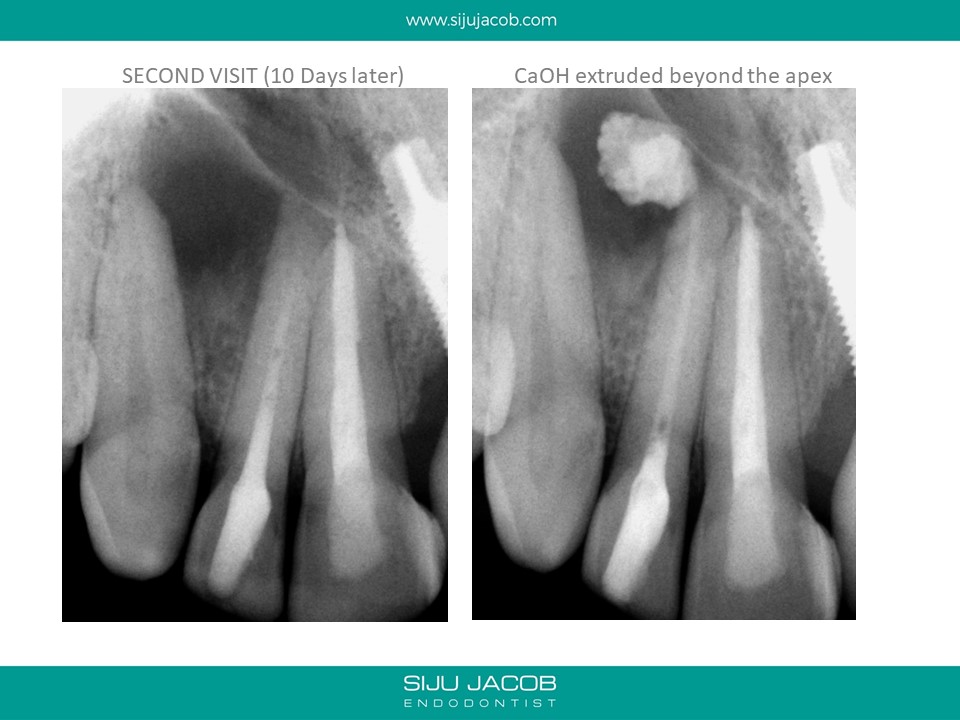

This patient was from The U.S. I re-treated a lateral incisor tooth of his while he was in Bangalore. He then went back to U.S. I received a mail from him two years later saying that the tooth we did was hurting. I thought that maybe, the lesion had recurred. I referred him to an Endodontist in the u.s who forwarded the radiograph to me. The lateral that I re-treated had healed well. It was an old central Incisor that had been treated much earlier that had fractured.